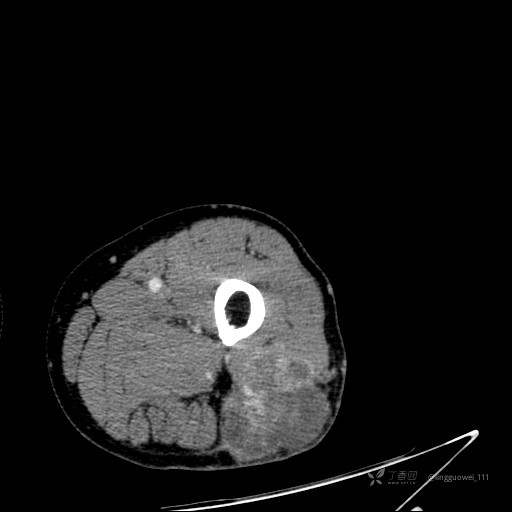

患者性别:男,85岁。发现大腿软组织肿块1年,增大3月,良性还是恶性?只有CT,能诊断正确吗?

增强动脉期